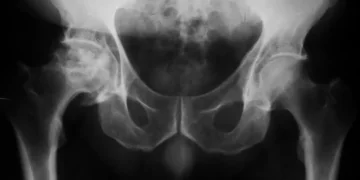

В наше время рентгенография является наиболее распространённым методом для диагностики состояния скелета. Именно на основании её результатов определяется последующее лечение.

- Рентген тазобедренного сустава позволяет оценить состояние суставных поверхностей.

- Помогает выявить наличие переломов и травм в области таза и бедра.

- Позволяет диагностировать дегенеративные изменения, такие как остеоартрит.

Рентгеновское обследование позволяет обнаружить такие заболевания, как артрит, артроз, некроз, переломы бедра, новообразования в руках, различные деформации в тканях и многое другое. Важно правильно выполнять рентген тазобедренного сустава и верно интерпретировать его результаты, так как проблемы в этой области могут привести к резкому ухудшению работоспособности и даже вызвать инвалидность.

Рентген тазобедренного сустава является важным инструментом в диагностике различных заболеваний и травм этой области. При проведении рентгенографии я обращаю внимание на множество факторов, таких как правильная позиция пациента и выбор подходящих проекций. Это позволяет мне получить максимально информативные изображения, которые могут выявить изменения в костной структуре, такие как остеоартрит, переломы или опухоли.

В настоящее время практически каждая медицинская организация оснащена рентгеновским кабинетом. Основное преимущество данной процедуры в сравнении с другими — это полное отсутствие боли. Специальные машины сконструированы так, что рентгеновские лучи направляются строго в область исследования. Они без труда проходят через мягкие и костные ткани, отображаясь в виде черно-белого изображения на специализированной пленке или экране компьютера.